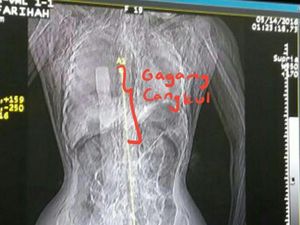

Eno Fariah (18) mendapatkan kekerasan sebelum akhirnya dibunuh secara keji oleh 3 tersangka dengan menggunakan cangkul serta garpu.